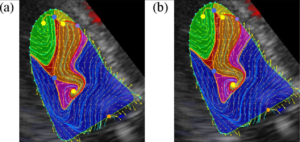

Computational Extraction of Topological Vortex Structures from Echocardiography Blood Flow Data